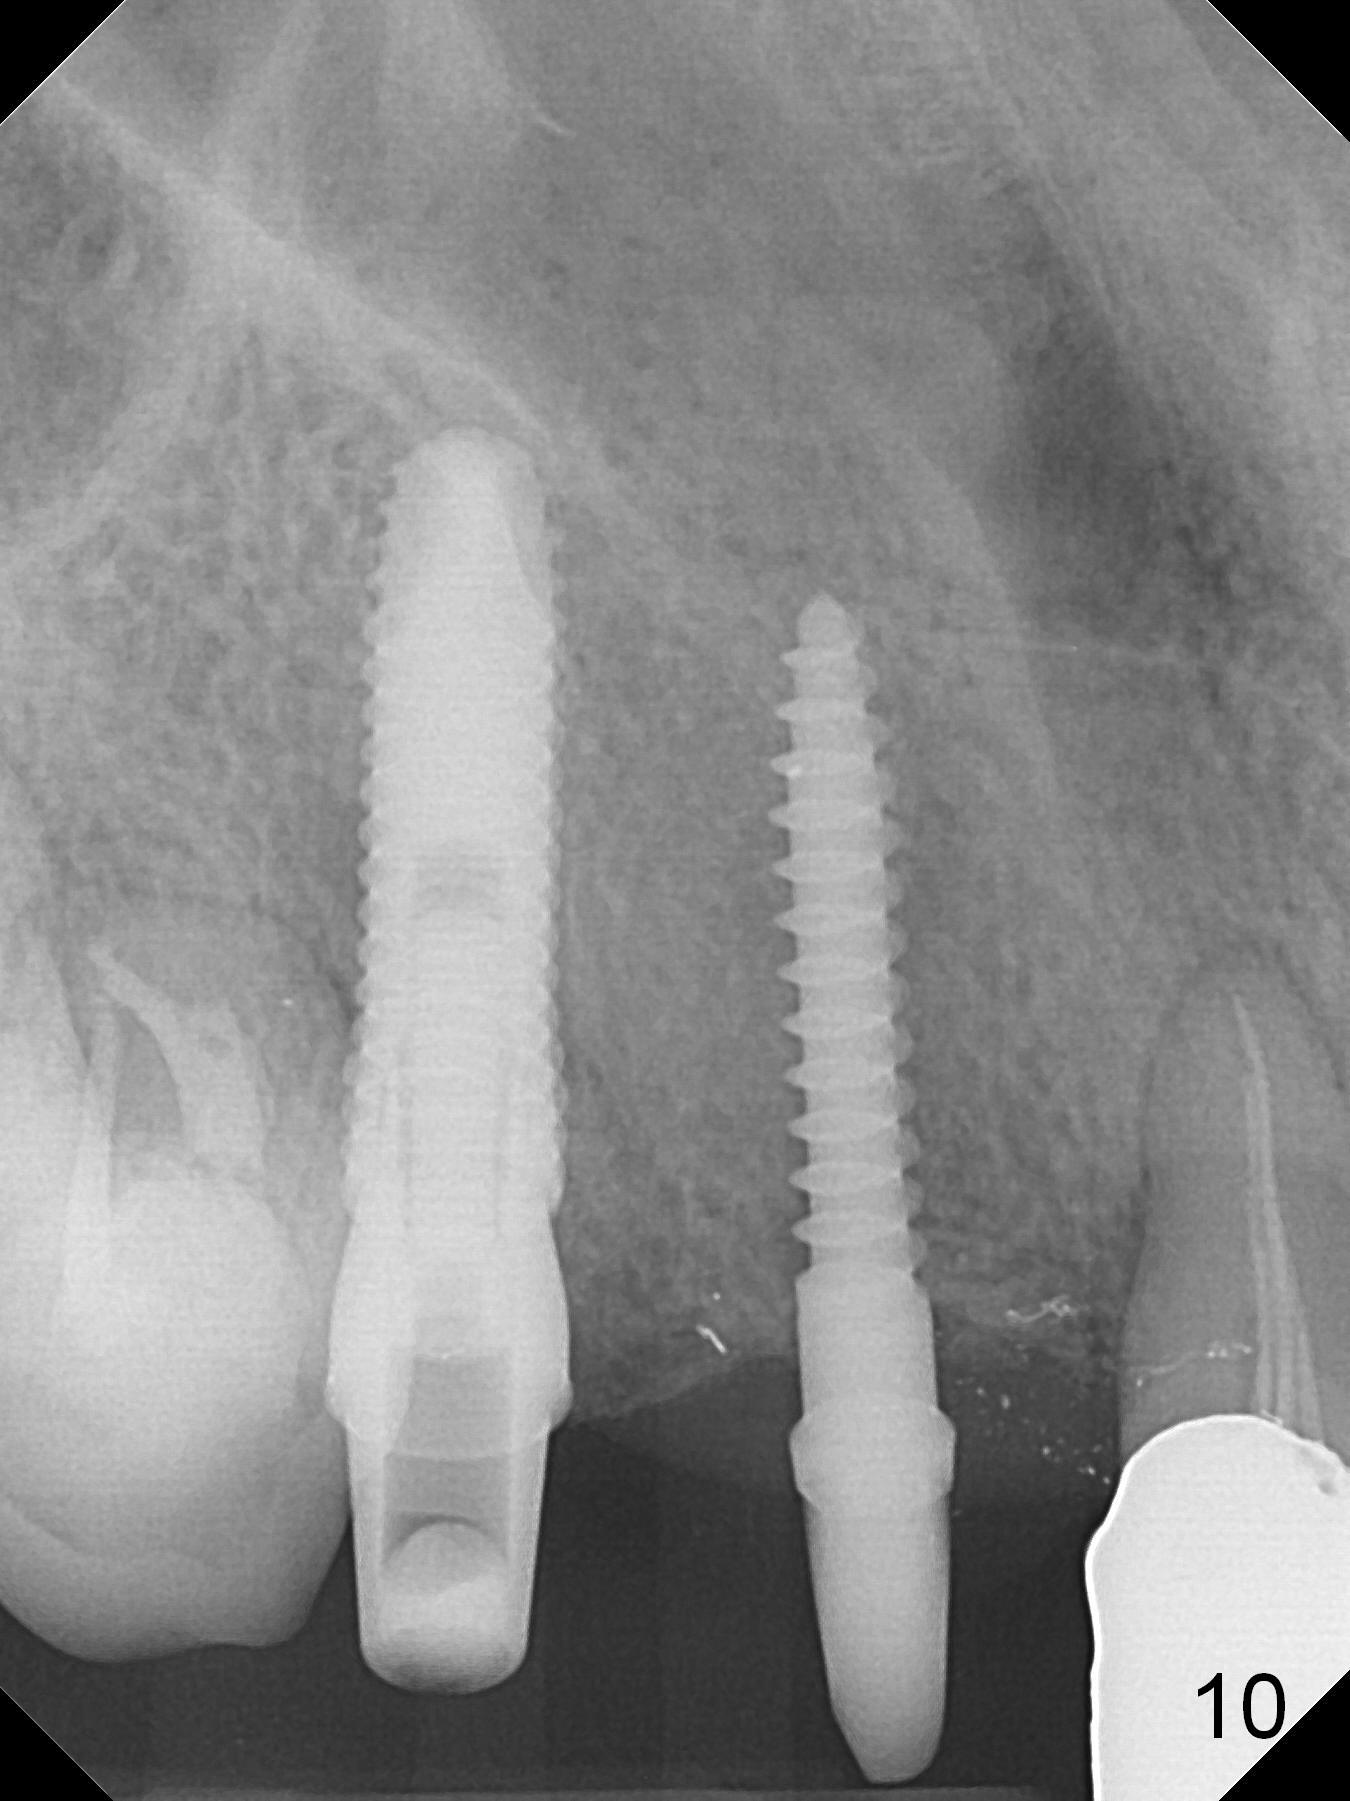

When the bridge is sectioned between #7 and 8, the tooth #6 is found non-salvageable (Fig.1). Incision shows the atrophic buccal plate at #7 (Fig.2 arrowheads); to prevent the same feature from happening at #6 with thin buccal plate, the most buccal portion of the root is preserved (socket shield (Fig.2-4: *)). The initial osteotomy is established in the palatal slope at #6 (Fig.5 circle) with 1.5 mm drill (Fig.6,7). A portion of the root is visible in Fig.6 (arrowheads). After sequential osteotomy with 2 mm, 3 mm (Fig.8) and 3.2 mm drills, a 4x15 mm implant is placed (Fig.10). To accommodate the cross bite, the coronal portion of the implant (Fig.9 white circle) is positioned close to the socket shield. It appears that the shield prevents the implant from encroaching the buccal plate.

Since the ridge at #7 is ~ 4 mm, a 2.5x14 mm 1-piece implant is placed (Fig.8) after 1.2 mm (Fig.7), and 1.5 mm drills at 12 mm and 2 mm drill at 8 mm. Later the implant is placed deeper (Fig.10). There is no bone loss 7 or 12 months postop, respectively (Fig.11,12). After Diode gingivectomy, there is papillary formation (Fig.13). No provisional is provided after impression (with the abutment torqued at #6) for oral hygiene. With access holes at #6 and 7, crowns are bonded with minimal residual cement (Fig.14 <, which is removed later). There is no hard (Fig.15,16) or soft (Fig.17 *) atrophy 26 months postop, i.e., 13 months post cementation, due to the presence of socket shield (Fig.15 <, as compared to Fig.1). In fact the tooth #8 has mobility and fremitus (short root/poor crown/root ratio, Fig.16); occlusal adjustment is done 13 months post cementation. The crown is dislodged 2 years 1 month post cementation; a prefabricated post is being tried in (Fig.18). There is no atrophy, bone loss or infection at #6 (with socket sheath (*)) or 7 two years 5 months post cementation (Fig.20-27).